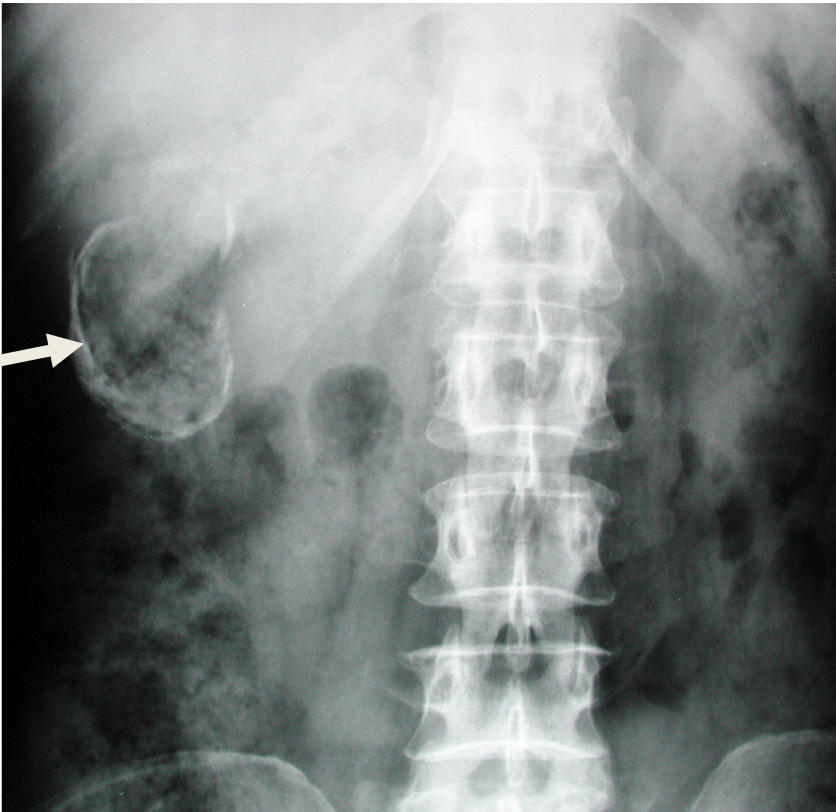

Can lead to porcelain gallbladder, which is associated w/ gallbladder carcinoma (20% of the time)

Porcelain gallbladder